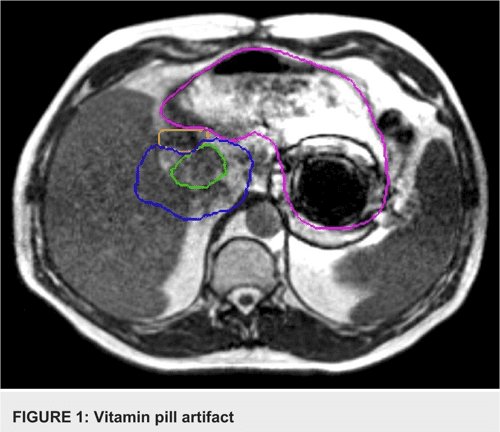

@I_F32_I The iron on the cereal clumps and generates artifacts on the imaging process, the iron particles are too small to be able to be yanked.

I always wondered what happened to people who ate cereal with added in supplement iron dust if they went to the MRI. Like surely the fact it's fine grit doesn't stop it from being yanked full strength out of the side of your stomach?